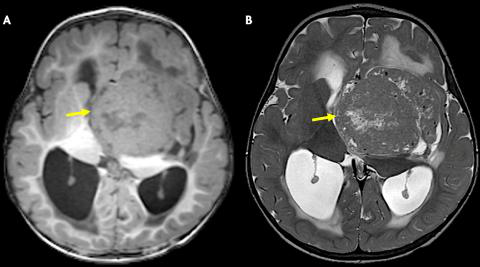

二周:T1WI(A)和T2WI(B)轴位磁共振图像显示肿块为T1等信号(相对于皮质)和T2低信号。肿块导致梗阻性脑积水,导致中度侧脑室扩大和室周水肿。